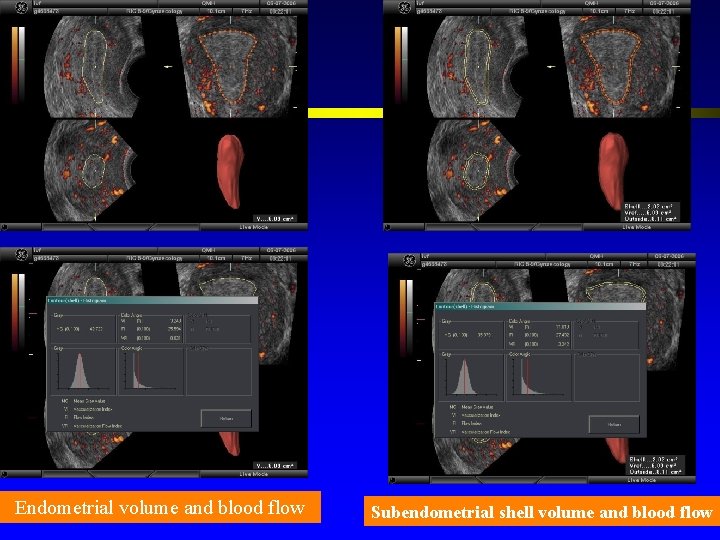

Endometrial blood flow l. A good blood supply towards the endometrium is essential for normal implantation.

Endometrial volume and blood flow Subendometrial shell volume and blood flow